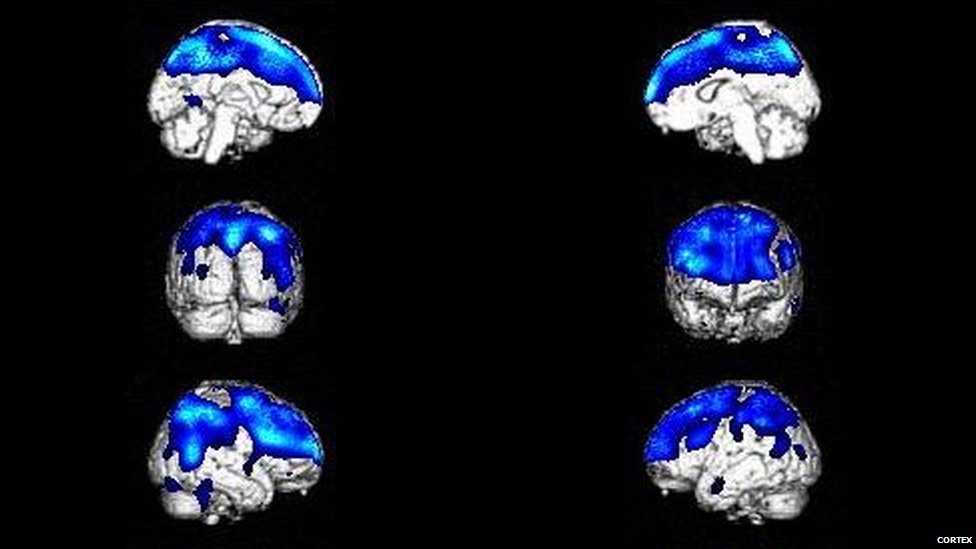

Un estudio realizado en 2010 por el Instituto Nacional de Neurología y Neurocirugía de México halló que el síndrome suele ser el resultado de dos factores que se combinan.

Los indicios neurológicos incluyen un índice metabólico muy bajo en regiones del cerebro responsables de la introspección, el achicamiento o aumento del cerebro y el daño a la parte del cerebro que está detrás de la frente, que controla los pensamientos, el razonamiento y el comportamiento.